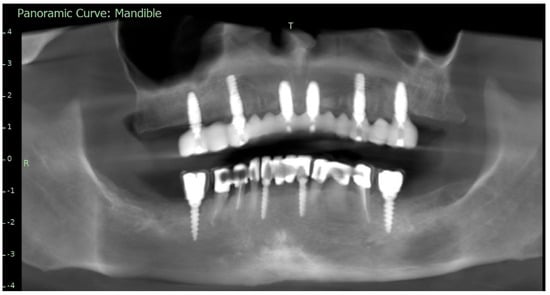

To verify the implant positions and the accuracy of the prosthetic fit, a control CBCT scan was obtained after the delivery of the early provisional restoration. Radiological evaluation confirmed stable positioning of the implants and correct seating of the prosthesis (Figure 11 and Figure 12).

The definitive prosthesis was delivered to the patient after laboratory verification. Intraoral evaluation confirmed accurate seating, passive fit, and proper occlusal relationships. Phonetics and aesthetics were reassessed and found to be satisfactory, consistent with previous retrospective data showing high survival rates and patient satisfaction with zirconia-based full-arch prostheses [28]. A panoramic radiograph was obtained at the time of prosthesis delivery to confirm the correct seating of the framework–zirconia assembly on all supporting implants, as well as to verify stable peri-implant bone conditions.

Figure 11. Control CBCT scan obtained after the delivery of the early full-arch provisional restoration.

Figure 12. Control CBCT scan obtained after the delivery of the early full-arch provisional restoration.